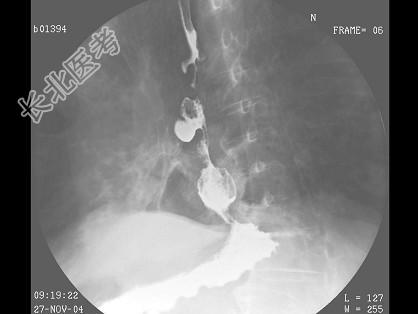

- 单项选择题男,71岁, 脾大、腹水、肝管结石2年,结合图像, 最可能的诊断为 ( )

E、食管癌